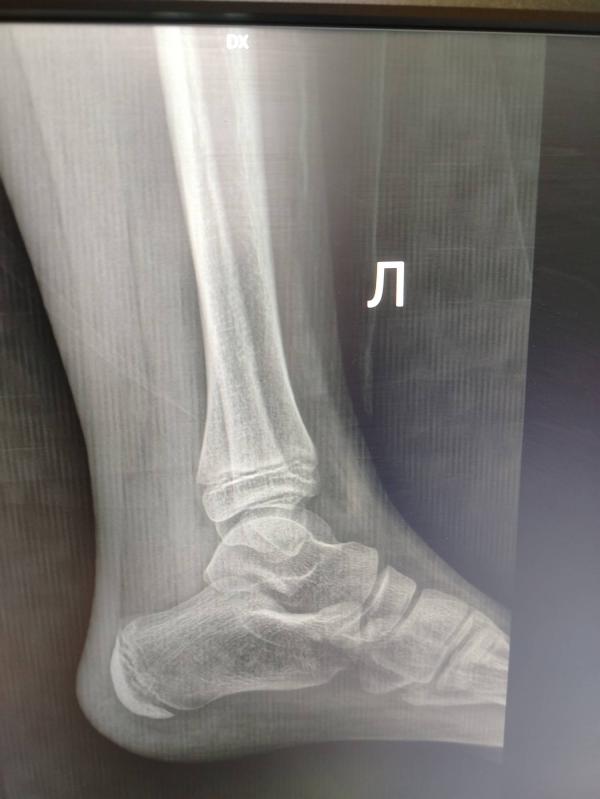

Девочки, может есть среди нас врач, который по снимку может определить повреждения ноги. Дочь ещё 13го числа на батуте сильно потянула ногу. Ездили в травму. Врач по снимку сказал растяжение сильное. Ноге, конечно, лучше, синяк меньше стал и отёк уменьшается. Но уже так долго не проходит. Думаю, надо ещё к кому-то ехать. Может он плохо посмотрел.

У меня так же год назад было, на вид кошмар отечно синий, по итогу повреждения кости нет, просто сильное растяжение. Но до сих пор там где косточка справа на правой лодыжке небольшая припухлость и не дай боже не так наступить или подвернуть, отекает и болит. Ну и погоду теперь по суставу этому можно предсказывать🤭🙈🤦🏽♀️

Отек от связок дольше держится, чем от перелома. И в целом восстановление дольше и последствия тяжелее